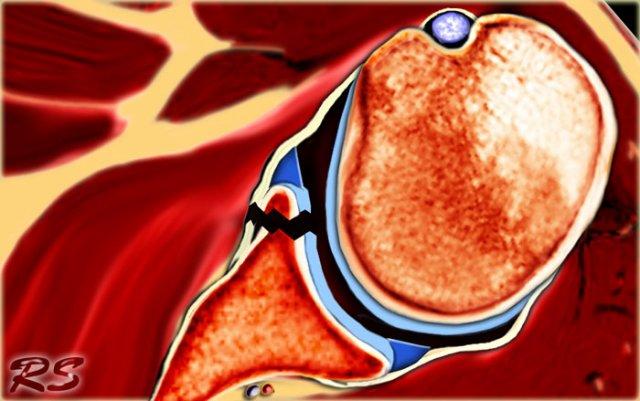

Sự di lệch của chỏm xương cánh tay ra trước-dưới gây tổn thương bờ trước-dưới của ổ chảo tại vị trí 3 – 6 giờ (đánh dấu màu đỏ).

Đặc biệt ở bệnh nhân trẻ tuổi, điều này dẫn đến gãy xương Bankart hoặc tổn thương Bankart, là rách sụn viền trước-dưới.

Hậu quả là gây mất vững khớp và trật khớp tái phát.

Tổn thương Bankart và các biến thể như Perthes và ALPSA là các chấn thương ở sụn viền trước-dưới.

Các tổn thương này luôn nằm ở vị trí 3-6 giờ vì chúng được gây ra bởi trật khớp ra trước-dưới.

Bong tách sụn viền trước-dưới (vị trí 3-6 giờ) với rách hoàn toàn màng xương bả vai phía trước, có hoặc không kèm mảnh xương ổ chảo. - Bankart ngược (Reverse Bankart)

Có hình ảnh bong tách sụn viền trước-dưới (vị trí 3-6 giờ) với rách hoàn toàn màng xương bả vai phía trước.

Mũi tên chỉ vào màng xương bị gián đoạn.